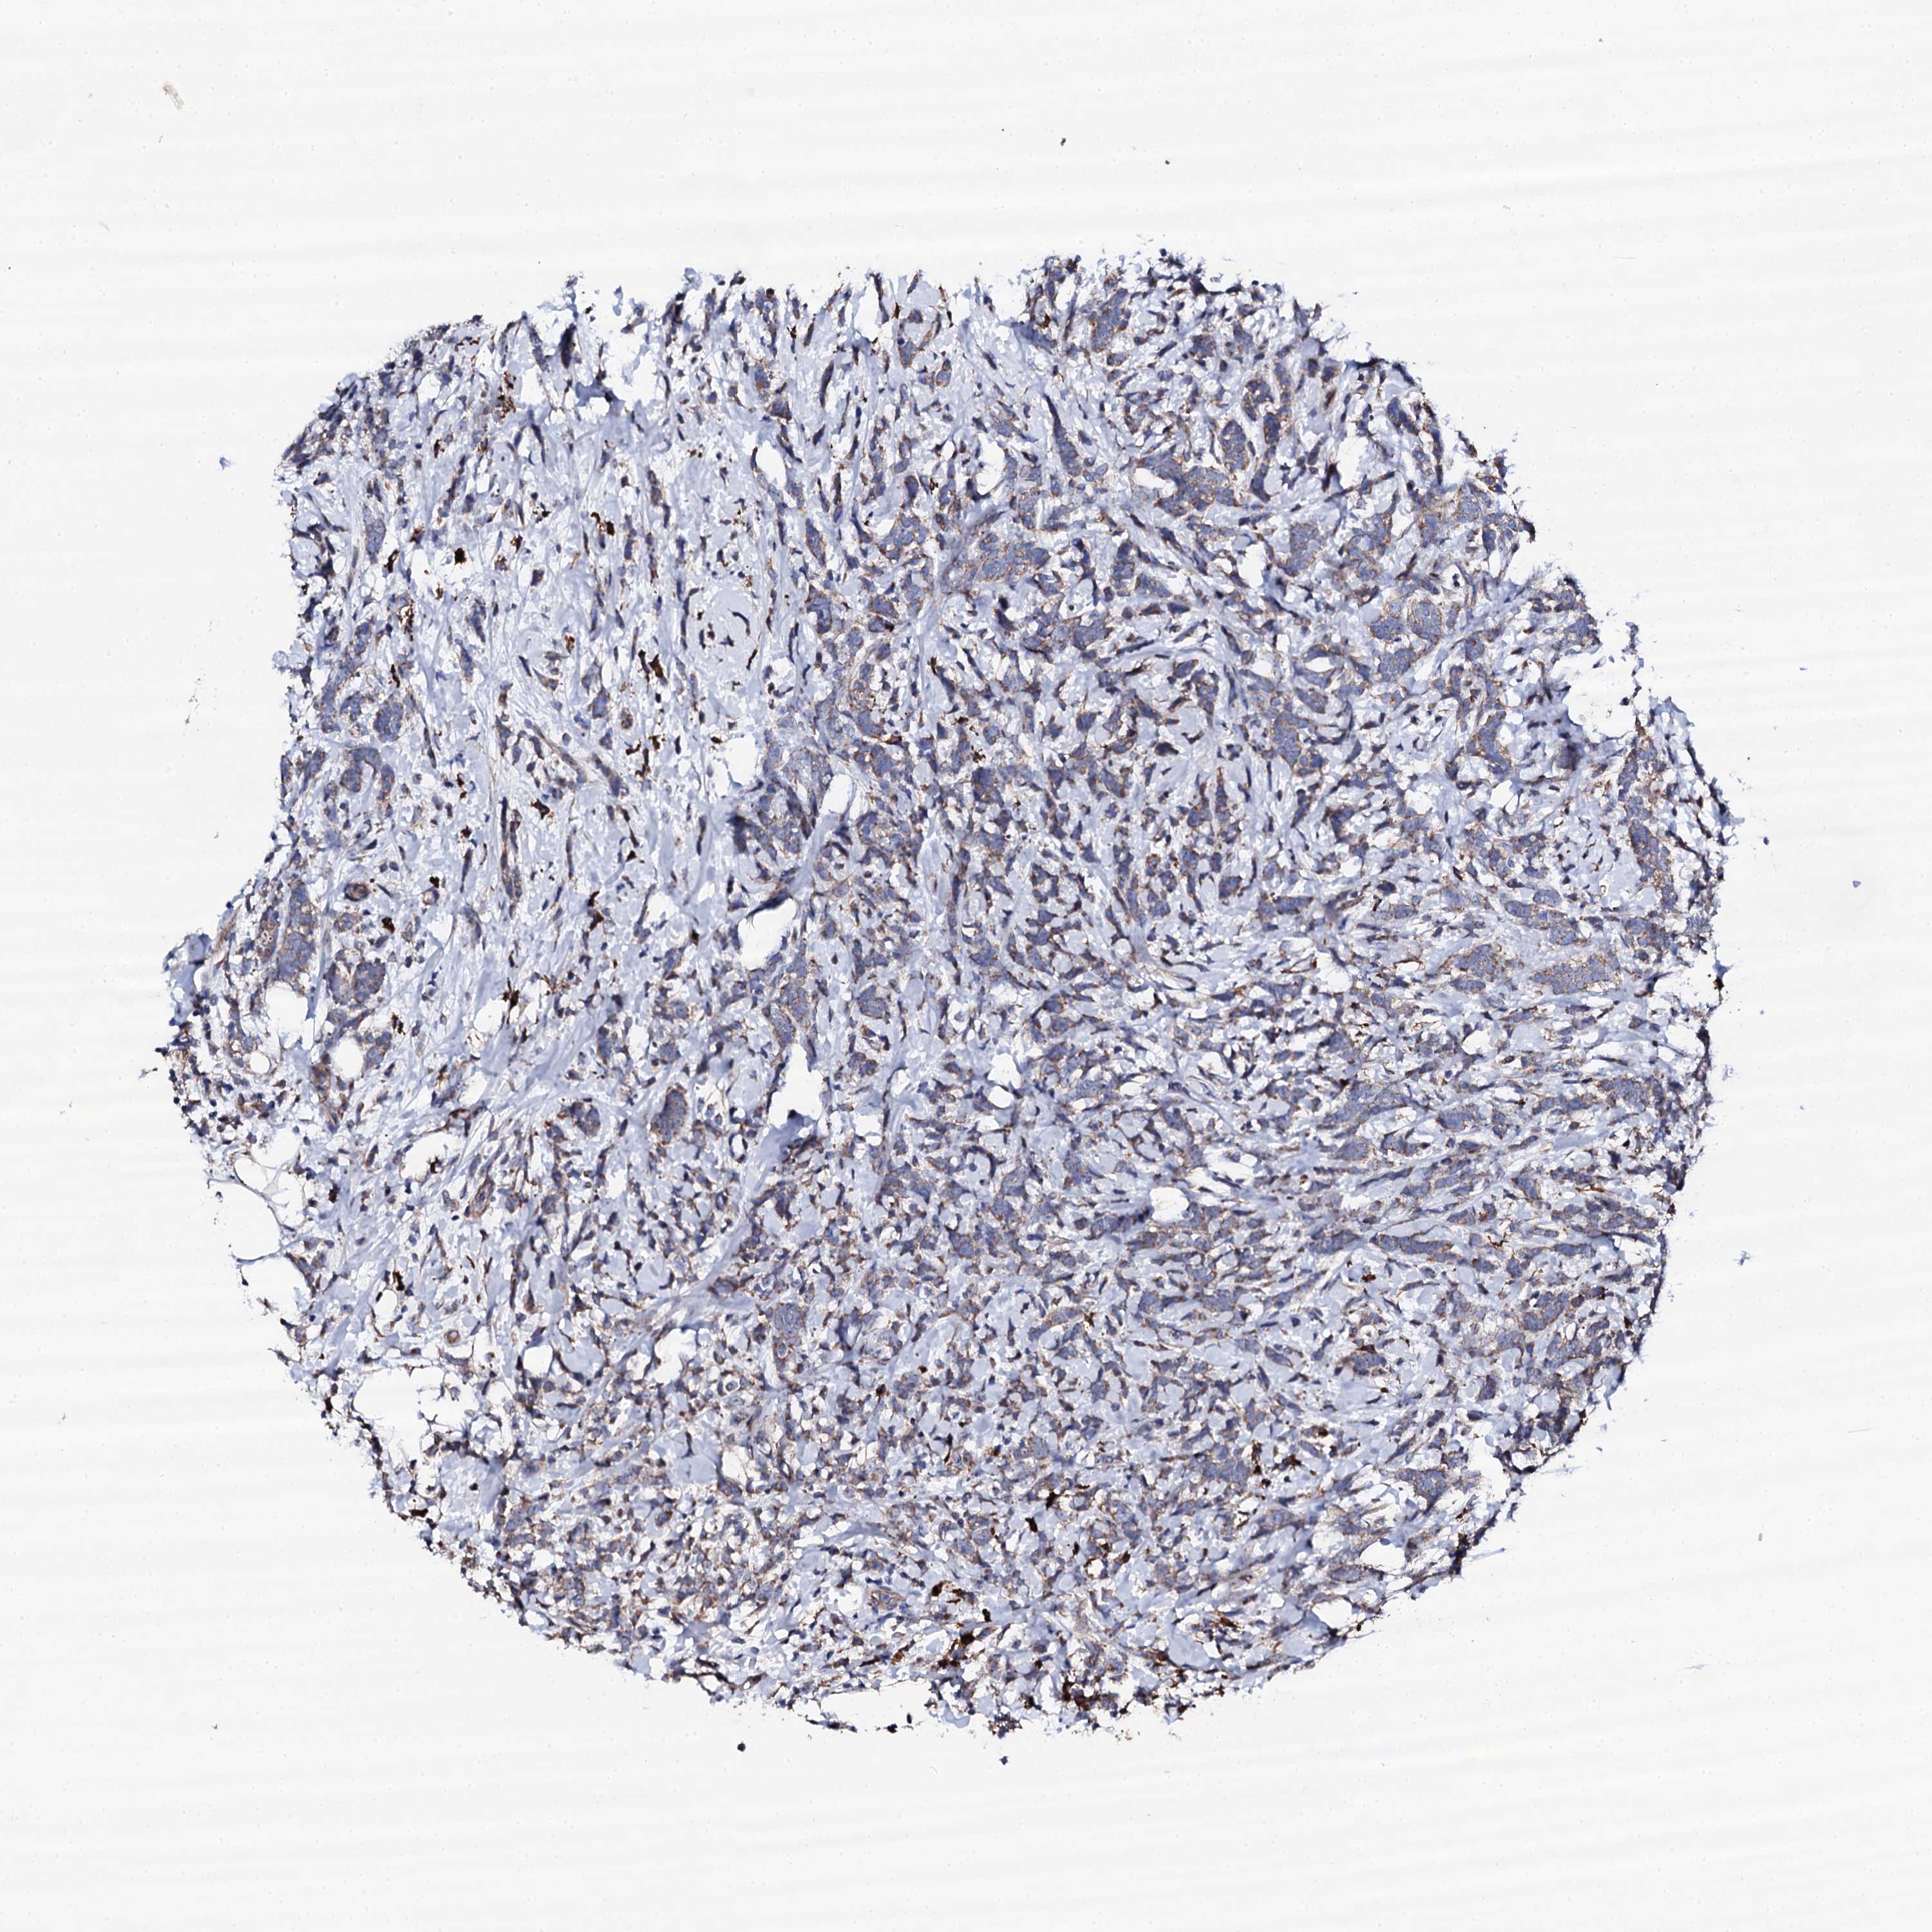

CANCER BREAST CANCER Show tissue menu

BRCA TCGA BRCA VALIDATION PROTEIN EXPRESSION

ANTIBODIES

AND

VALIDATION